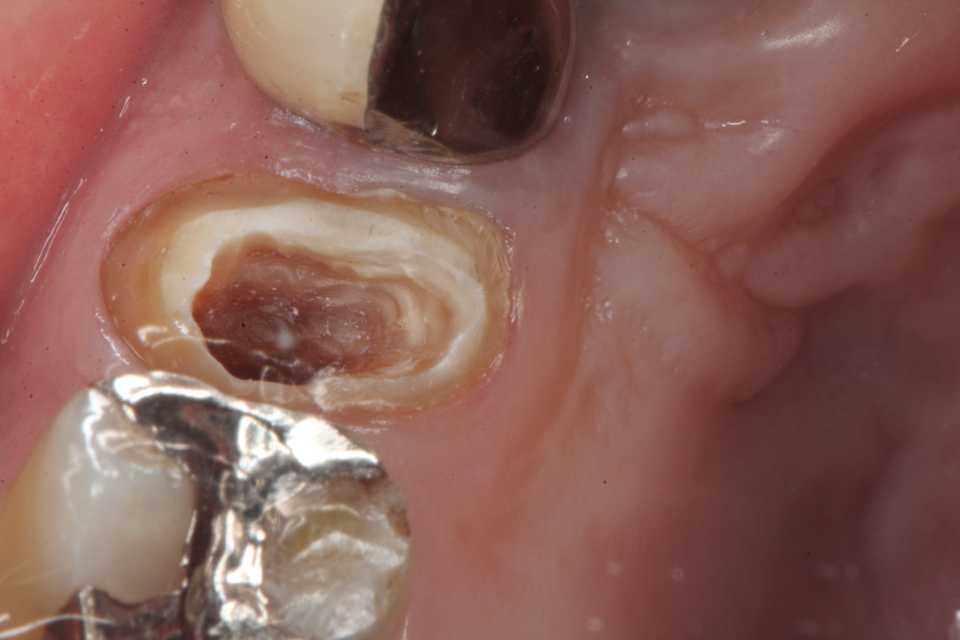

残根上のCR8 2025.10.28